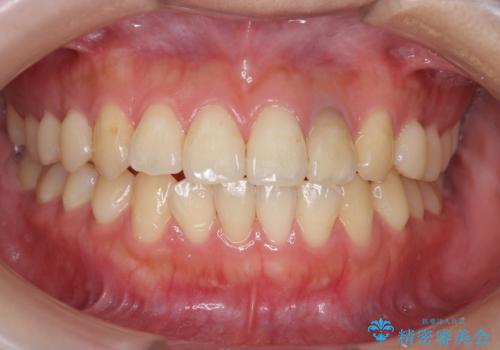

歯の色が自然な感じに白くなり、きれいになったと満足していただけました。